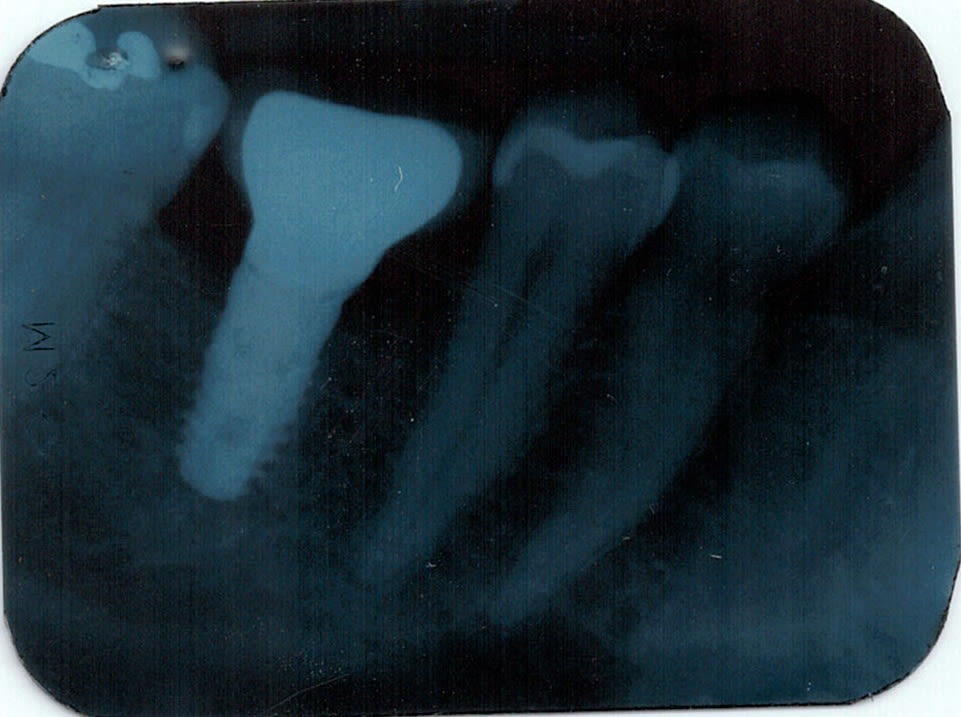

Bonsoir

Pouvez vous m'aider a identifier ces implants. La seule chose que je sais, c'est que ce n'est pas tout jeune !

Merci

Vtui8qni2kewwypr4hhdkct1r12p - Eugenol

Faudrait démonter pour être certain…..parce que j’arrive pas à voir la connexion…

En 1 je dirais du Sterioss

https://www.spotimplant.com/fr/implants-dentaire/steri-oss/steri-oss-original-non-hex

En 2, des 3M ESPE

https://www.spotimplant.com/fr/implants-dentaire/espe-3m/fixture

Pranou

11/06/2024 à 13h55

Merci Pluton, je vais déposer la prothèse pour essayer d'avoir plus d'informations